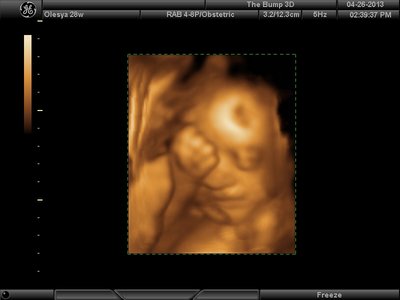

Еще одна, качество ужасное..

image.jpg [ 60.32 КБ | Просмотров: 1449 ]